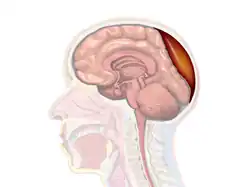

Epidural hematoma is when bleeding occurs between the tough outer membrane covering the brain (dura mater) and the skull.[4] Often there is loss of consciousness following a head injury, a brief regaining of consciousness, and then loss of consciousness again.[2] Other symptoms may include headache, confusion, vomiting, and an inability to move parts of the body.[1] Complications may include seizures.[1]

Epidural hematomas usually appear convex in shape because their expansion stops at the skull's sutures, where the dura mater is tightly attached to the skull. Thus, they expand inward toward the brain rather than along the inside of the skull, as occurs in subdural hematomas. Most people also have a skull fracture.[3]